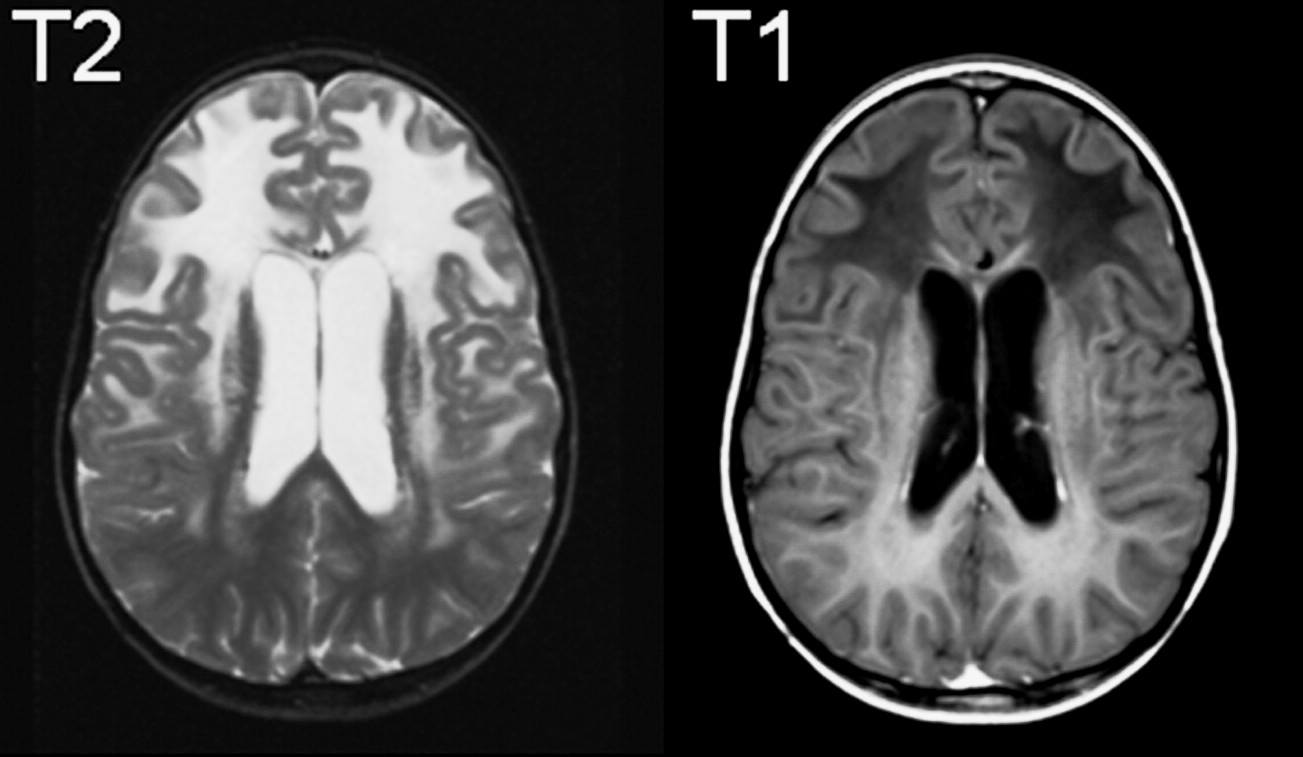

1. Trong hệ thần kinh trung ương

và ngoại biên nhiều sợi thần kinh được bọc bởi bao myelin; nhờ đó các xung thần kinh được dẫn truyền nhanh hơn. Trong một số bệnh lý, bao myelin bị ảnh hưởng sẽ làm gián đoạn sự dẫn truyền thần kinh của bất kỳ thành phần nào trong hệ thần kinh và biểu hiện triệu chứng.

Trong hệ thần kinh trung ương, myelin được hình thành bởi các tế bào thần kinh đệm ít nhánh, còn ở khu vực ngoại vi myelin do các tế bào Schwann tạo ra, myelin ở hai khu vực này khác về mặt hóa học và miễn dịch. Do vậy, một số bệnh myelin có khuynh hướng ảnh hưởng chủ yếu đến các dây thần kinh ngoại vi

2. Sự thoái hóa myeline thường

là thứ phát sau khi nhiễm trùng, thiếu máu cục bộ, bệnh lý chuyển hóa, di truyền hoặc ngộ độc (ví dụ rượu, ethambutol). Bệnh lý thoái hóa myelin nguyên phát thường không rõ nguyên nhân, giả thuyết rằng do cơ chế tự miễn vì bệnh lý xuất hiện sau khi nhiễm virus hoặc tiêm chủng.

Myelin có xu hướng mất từng đoạn hoặc từng mảng, ảnh hưởng đến nhiều khu vực cùng một lúc hoặc tuần tự. Myelin được tái cấu trúc bằng cách sửa chữa và tái tạo và chức năng thần kinh phục hồi hoàn toàn. Tuy nhiên, sự thoái hóa sợi trục và tế bào thần kinh sẽ xảy ra sau khi myelin mất diện rộng; cả hai tổn thương này đều không thể đảo ngược.